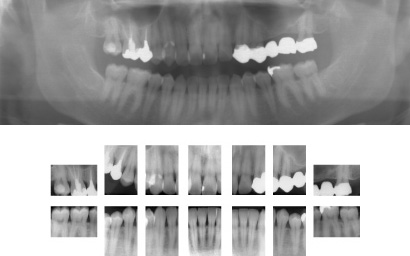

1. 口腔内の検査

レントゲン撮影

歯槽骨(歯を支える骨)の状態や、歯茎の奥の歯石をチェックします。